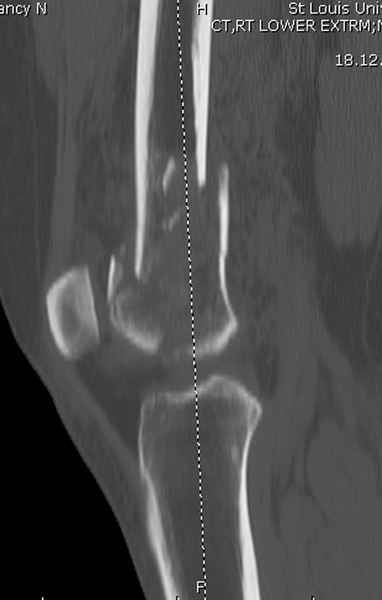

Приветствую всех коллег!!Во первых слева хотелось бы видеть четкую боковую проекцию а лучше КТ. По р-мам есть сомнения насчет повреждения суставной поверхности. При подобных переломах даже внутрисуставных без смещения хорошие результаты показал закрытый ретроградный остеосинтез универсальным бедренным стержнем Деост.Кстати при внутрисуставном переломе возможно применение вместо винтов стягивающих болтов!!(См. метод.Деост).При переломе справа также стержень Деост. Однако без открытия Вам не удастся устранить интерпозицию, только промучаетесь!Из минимального разреза удалите интерпозициб и фиксируйте стержнем. Причем универсальный стежень Деост позволяет фиксировать дистально минимум на трех уровнях!

Уважаемые коллеги! От имени Алексея Смирнова всем спасибо за обсуждение. Больной прооперирован. Снимки в приложении.